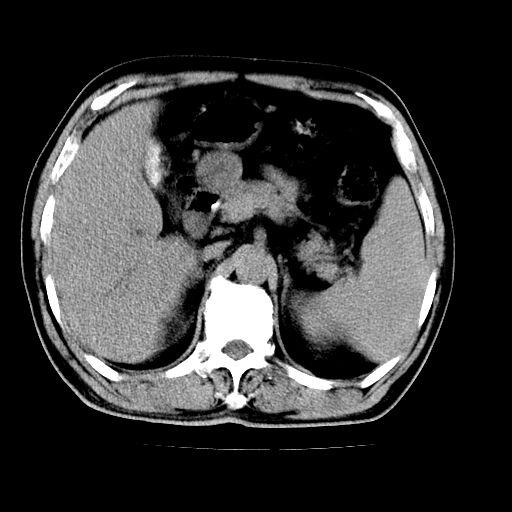

男,66岁,上腹部不适、黄染一周。彩超示:肝左叶占位,肝内胆管扩张,胆总管扩张,胆总管占位?

肝左叶不规则软组织肿块影,边缘不规整邻近肝实质受累分界不清;肝内胆管(左叶)明显扩张成“软藤状”,诊断:肝左叶胆管细胞癌。

肝左叶占位性病变,并胆管扩张,符合胆管细胞癌ct表现,门脉左支受累,左肾囊肿。窗宽太窄了,其他的看不清

左叶胆管细胞癌累及胆总管,门脉左支受侵,慢性胆囊炎胆结石,左肾小囊肿

肝左叶不规则软组织肿块影,边缘不规整邻近肝实质受累分界不清;肝内胆管(左叶)明显扩张成“软藤状”,诊断:肝左叶胆管细胞癌。胆囊钙乳症。